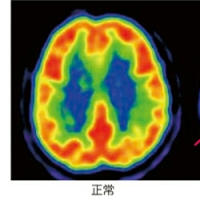

Aβと脳老化-軽度認知症の意味するもの

#アルツハイマー病

#認知症

アミロイド・ペプチドとその産生‐悪玉Aβ

脳老化の特異性とその本質

アルツハイマー病の最大の謎